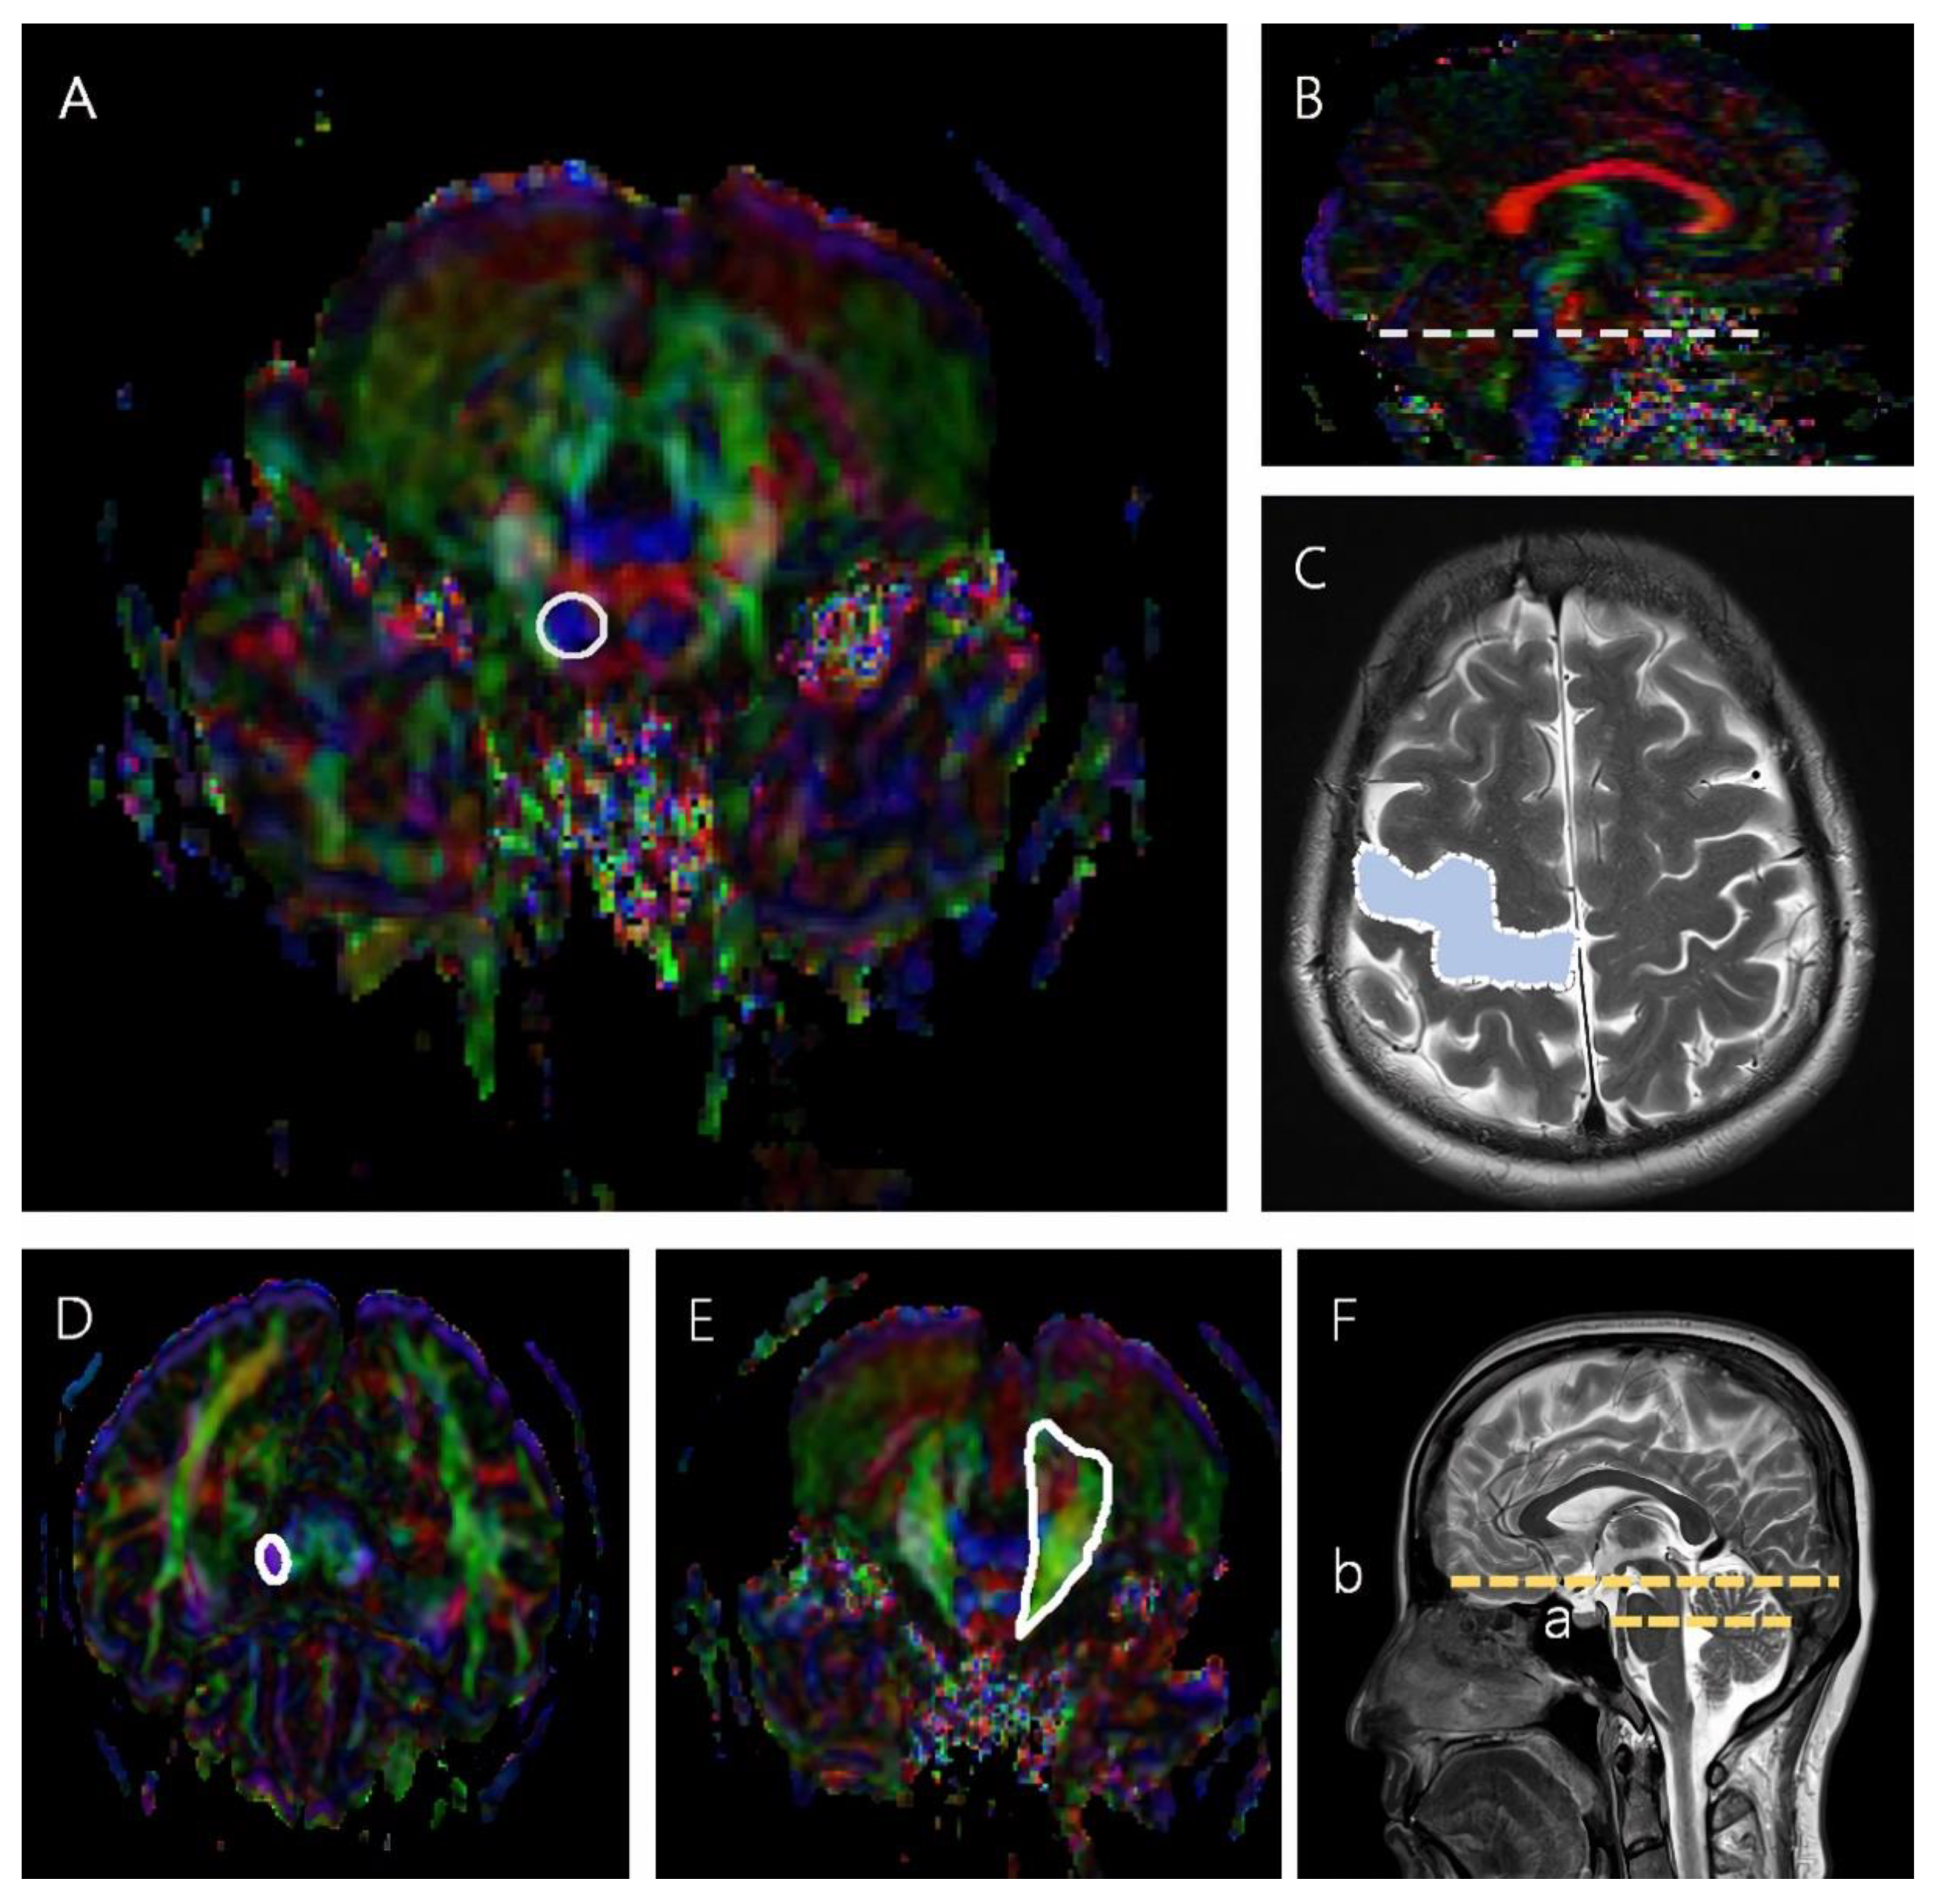

The CST was reconstructed using two ROIs in which the seed ROI was placed on the mid-pons portion of the CST in the axial plane, and the target ROI was the M1 [4,19]. When reconstructing the CPCT, the seed ROI was placed on the middle cerebellar peduncle, and the target ROI was placed on the cerebral peduncle of the contralateral side (Figure 1) [10,20].

Figure 1.

The seed and target ROIs used to reconstruct the CST and CPCT. (A) The region inside the solid line represents the seed ROI in the CST, mid-pons, in an axial color map. (B) The dotted line represents the mid-pons level in a sagittal color map. (C) The blue region in the dotted line represents the target ROI in the CST in an axial brain MRI scan. (D) The region in the solid line represents the target ROI in the CPCT at the cerebral peduncle in an axial color map. (E) The region in the solid line represents the seed ROI in the CPCT at the middle cerebellar peduncle, mid pons, in an axial color map. (F) (a) is the slice level of the seed ROI, and (b) is the slice level of the target ROI in a sagittal brain MRI scan.